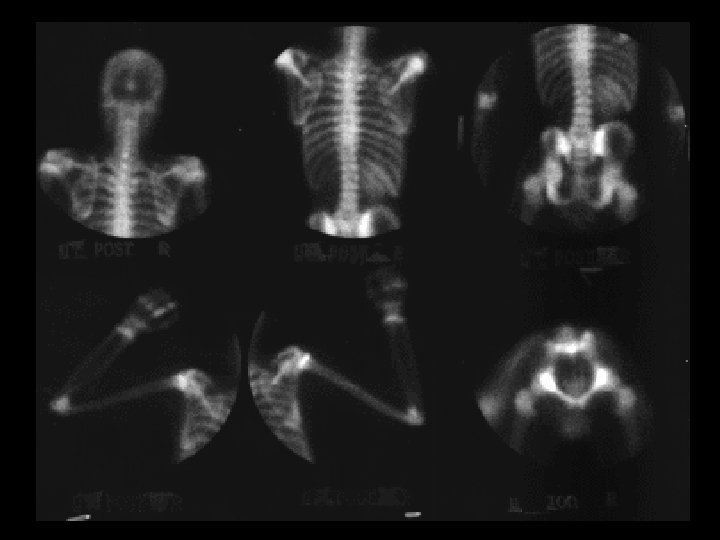

Neuroblastoma • Findings: – Bone scan shows increased uptake in the mid abdomen of a child – MR scan shows a corresponding soft tissue mass with scattered T 1 low sign foci = Ca 2+ • ddx: – NONE! – This is an Aunt Minnie!